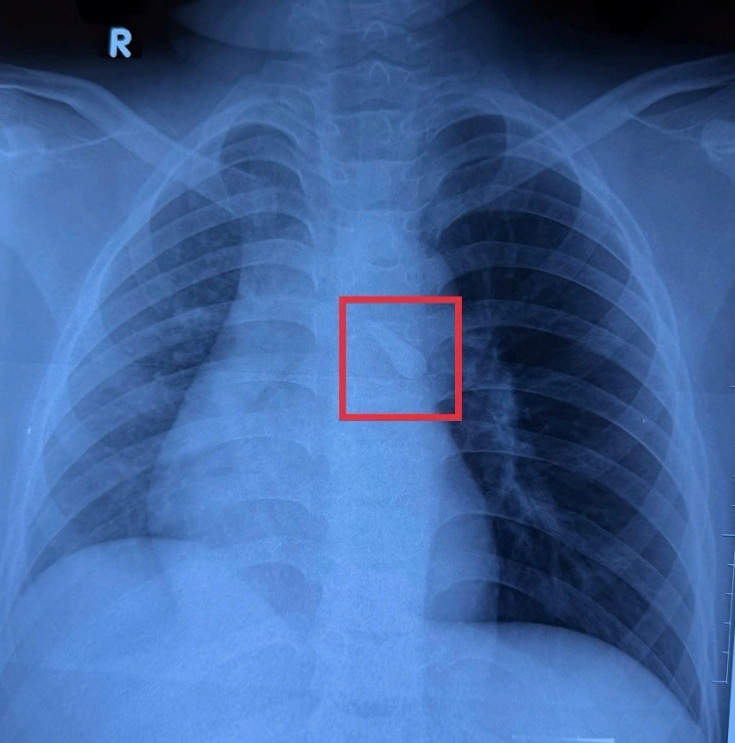

Ghi nhận trên phim Xquang cho thấy bé K. bị sặc dị vật vào khí quản sau tai nạn giao thông, ảnh BVCC

Ghi nhận trên phim X-quang cho thấy bé K. bị sặc dị vật vào khí quản sau tai nạn giao thông - Ảnh: Bệnh viện cung cấp

Kết quả chụp X-quang cho thấy khí quản của bé có một dị vật. Bác sĩ khai thác thêm bệnh sử và phát hiện tại nơi tổn thương vùng hàm mặt ghi nhận bé bị mất răng số 21. Bác sĩ nghĩ đến khả năng va chạm mạnh làm bé bị gãy răng, và hít sặc vào đường thở nhưng bé không cảm nhận được.